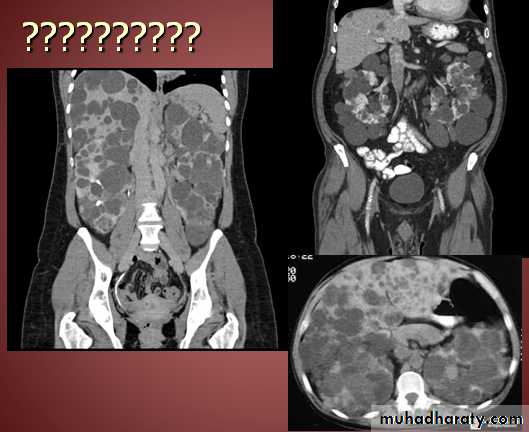

Hydatid cyst

Appear as large oval hypo dense area density of fluid with well defined margin , sometime at their periphery multiple flecks of calcification are seen at their periphery .

Hydatid cyst with daughter cyst , appear as multiple hypo densities rounded area within the main loculi with multiple rim of

calcification

Hydatid cyst within the liver

CT Scane

??????????????